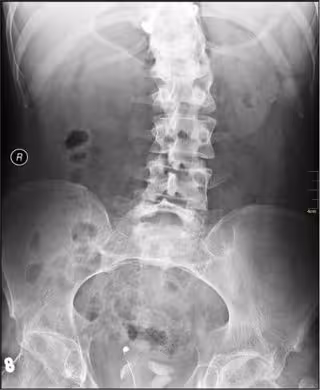

"Los resultados demuestran que 'microRNAs' circulantes en el plasma pueden servir como biomarcadores para la escoliosis idiopatica, lo que proporciona un nuevo método para diagnosticar y pronosticar esta patología, evitando irradiación repetitiva de rayos x para monitorizar la progresión de la escoliosis", ha destacado la jefa de la Unidad de Columna del Hospital Universitario y Politécnico La Fe, la doctora Teresa Bas.